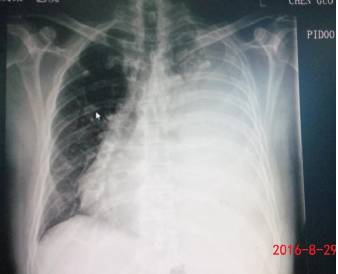

少量胸腔积液可以看到四边形征和正弦征,四边形征指胸腔积液时将胸膜

胸腔积液胸片典型图片

胸腔积液x线胸片图解